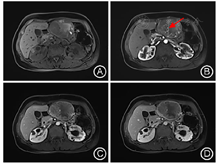

患者入院后查肝胆胰脾彩超提示:左肝混合回声团,肝癌待排。实验室检查提示:乳酸脱氢酶785 IU/L,乙肝核心抗体定量6.16S/CO,肿瘤指标无殊。查体:腹平软,剑突下轻微压痛、反跳痛。胸骨柄处肿胀明显,压痛阳性。MRI增强检查提示:肝左外叶占位,恶性肿瘤(肝细胞癌可能大)伴出血考虑(图1,图2)。为明确肿瘤转移情况,患者完善18F-FDG PET-CT检查提示:1.左肝外叶软组织肿块伴FDG代谢环形增高,首先考虑肝脏恶性病变;2.胸骨结核术后,胸骨柄右前方软组织结节伴钙化,首先考虑结核浸润(图3)。

由于HEAML内缺乏或极少含脂肪组织,MRI T1WI及同反相位上病灶内脂肪不易发现,当其增强表现与肝细胞癌(Hepatocellular carcinoma,HCC)重叠时,两者的鉴别尤为困难。本例HEAML病灶实质在反相位上未见信号减低,增强后延迟期信号低于周围肝实质,且可见环形强化的假包膜,因而容易在MRI影像表现上想到HCC的诊断。

有研究显示,HEAML富含迂曲扩张的厚壁血管,即增强后病灶内点条状血管影对两者的鉴别诊断有重要意义[8,9]。HCC的肿瘤血管主要为肝动脉,轮廓不光滑,血管不成熟、不连续,欠规则,走行僵直,门静脉期不显示,而HEAML中心血管为畸形静脉,表现为迂曲、流畅、光滑、粗细不等的强化血管,即肿瘤内"中心强化血管征",为HEAML特征性表现。因HEAML的肿瘤血管类型及含量不同,肿瘤的强化方式多样,主要分为两种:"快进快出"和"快进慢出"。在动脉期,由于HEAML富含大量血管和血窦,多数HEAML表现为在动脉期明显不均匀强化,这些血管多为静脉性血管,病理上证实为动脉期早显的静脉,影像上易误认为肿瘤供血动脉(图4A)。在门静脉及延迟期,血管网丰富、血管较细、管壁较薄、血流速度较快的病灶强化程度迅速降低,表现为"快出";少或无血管、血管较粗、管壁较厚的病灶,显像剂扩散至血管外间隙需要较长时间,表现为"慢出"[2,8]。本例病灶门静脉期肿瘤实质进一步强化,延迟期强化低于肝实质,可符合"快进快出"的强化模式,但又与门静脉期强化即低于肝实质的典型HCC影像表现有所不同。此外,当HEAML病灶足够大时,可压迫周围肝实质形成不完整的假包膜,病理上主要是由压缩的肝实质、稀疏的纤维化组织及小血管构成。虽然HEAML和HCC均可见到假包膜,但HEAML的假包膜出现的概率明显低于HCC[8]。Liu等[9]在分析比较HEAML和HCC的MRI特征研究中,发现HEAML中仅有20%出现假包膜,而HCC中则多数有假包膜征象(78.8%)。